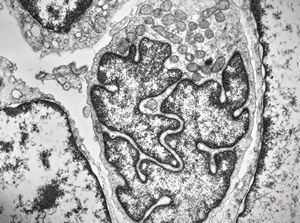

M, 70y. | mycosis fungoides - Sézary cell